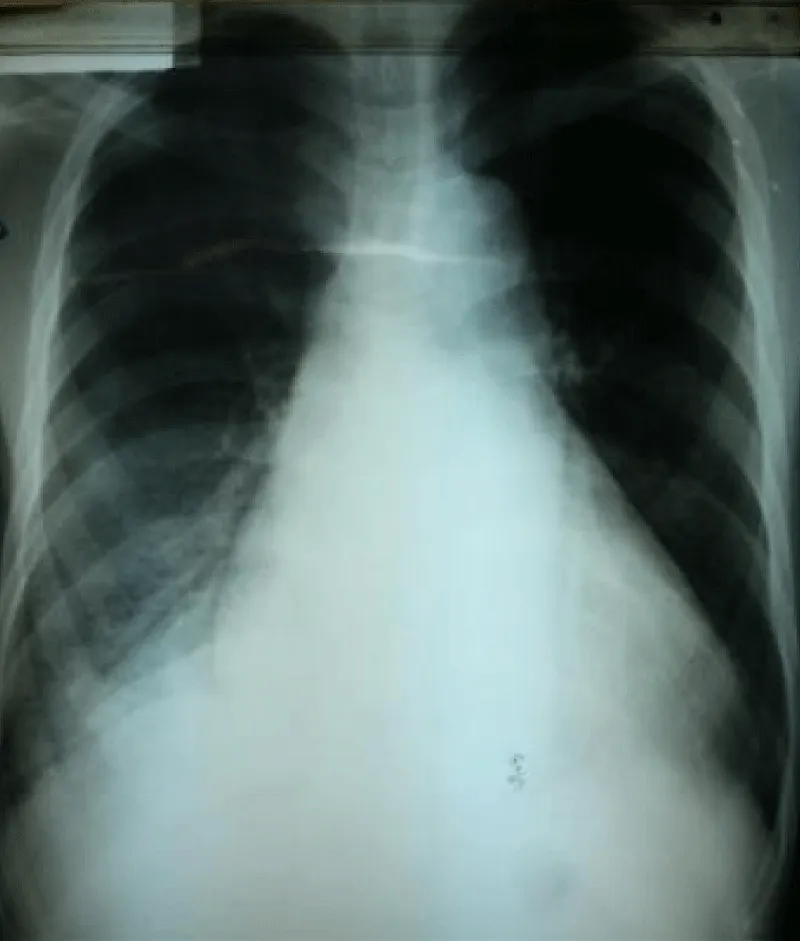

Transthoracic echocardiography (Figures 3,4) found a dilated aortic root (52 mm) with an ultrasound image of the intimal flap, and significant bi-ventricular dilation (left ventricular end-diastolic diameter of 72 mm). Systolic functions of both ventricles were severely impaired (LVEF of 24% and TAPSE of 10 mm). There was severe aortic regurgitation with a regurgitant orifice area of 35 mm². Dissection of an aortic aneurysm on dilated cardiomyopathy was diagnosed and confirmed by aortic CT scan (Figure 5); it was a type A aortic dissection with very severe dilation of the aortic root at the origin of the first branch of the supra-aortic trunks. A Type B dissection coexisted along, with an aortic dilation beginning far from the origin of the last branch of the supra-aortic trunks up to the iliac bifurcation. The Marfan disease was diagnosed despite the absence of genetic testing and a family history of the syndrome. An ophthalmological assessment could not be carried out. Medical treatment with diuretics, vasopressin amines, and analgesics was started and enabled slight improvement. The patient was later referred for surgical management through the financial support of a philanthropic sponsor. He was operated on March 7th, 2013 under cardiopulmonary bypass, using the Tirone David procedure. During surgery, the impression of two separate aortic dissections was confirmed: the former one of type B which previously went unnoticed, and the recent one of type A which determined the patient current clinical condition. After surgery, congestive heart failure was persistent, but during follow-up in the outpatient unit, the clinical condition remained stable under diuretic, ACE inhibitor, and oral anticoagulation. Unfortunately, the patient died four years later in 2017, due to poor medical follow-up.

Figure 3: Transthoracic heart ultrasound suprasternal incidence: note the aneurysmal dilatation of the ascending aorta, aortic leakage, presence of an intimal tear and intimal flap (arrow).